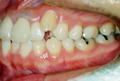

●主 訴 ― 叢生

●治療期間 ― 約3ヶ月

●治療内容 ― FLB舌側矯正装置、及びヘミオステオトミーによるスピード矯正(非抜歯ケース) |